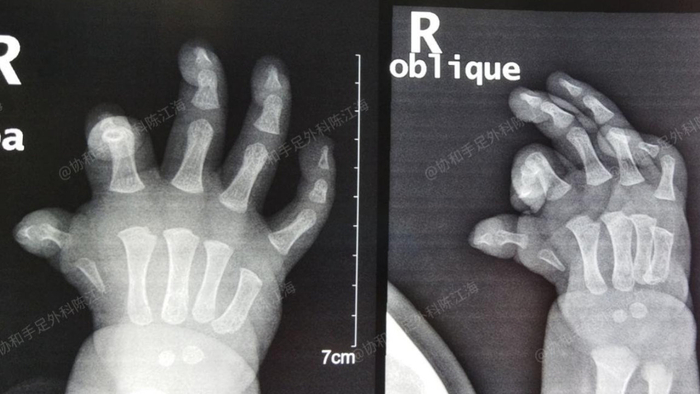

这是一个来自浙江的宝宝,他的右手拇指以前是IIIC型拇指发育不良,不会动。妈妈担心影响孩子的手部功能和心理健康,因此希望能够手术进行改善。在宝宝1岁多的时候,我们采用SMRT半掌骨移植重建的方法把漂浮拇指保了下来。如今宝宝右手拇指不仅长大了,而且功能也有了改善,抓握东西、拧“螺丝”都很不错。

漂浮拇,我们通常用SMRT半掌骨移植重建的方法来保指:

手术分为2期,第一期从患手第二掌骨取部分骨到第一掌骨上,搭好骨架。第二期肌腱转位手术,将环指指浅取肌腱移植到拇指上,重建拇指功能。两期手术要间隔3个半月左右,全程只在患手部位操作,对身体其他部位没有影响。